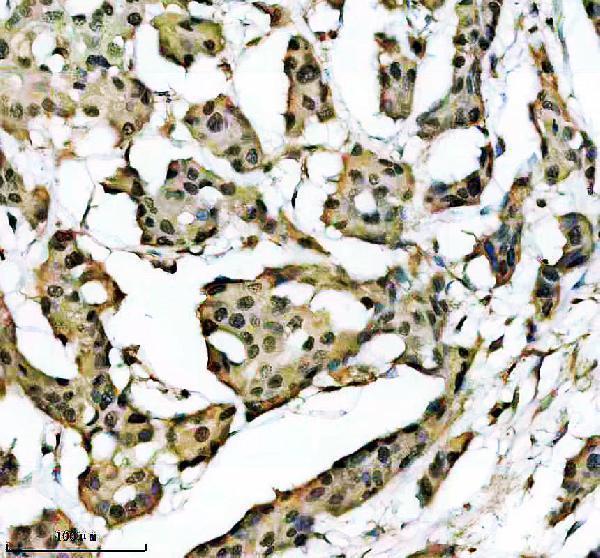

Facts about Zinc finger protein ubi-d4.

Might also have a role in the development and maturation of lymphoid cells (By similarity). Involved in the regulation of non-canonical NF-kappa-B pathway (PubMed:20460684).

Ubiquitous.

Nucleus. Cytoplasm.